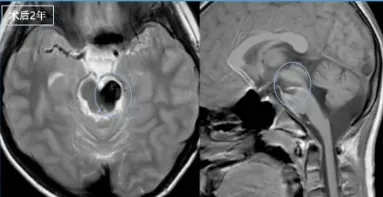

术后3年——顺利入学

阳阳已如期升入小学,开启全新的生活篇章。随访期间未见复发,此前的肢体无力和麻木症状也已明显好转。